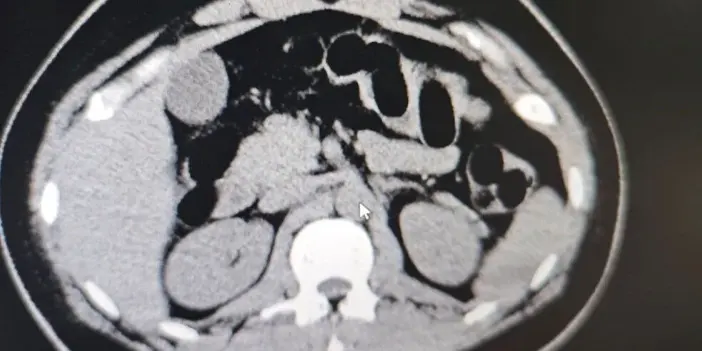

Tomografi Sonucunda Uyuşturucu Tespit Edildi

Hastanede yapılan iç beden muayenesi ve tomografi görüntüleri sonucunda, şüpheli şahsın midesinde uyuşturucu madde taşıdığı belirlendi. Muayene sonrasında şüphelinin midesinden toplam 84 kapsül içerisinde daralı ağırlığı 842 gram olan eroin ele geçirildi.